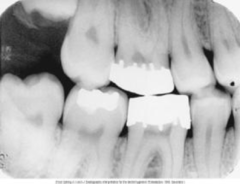

poorly contoured crowns

Front

Back

fixed bridge